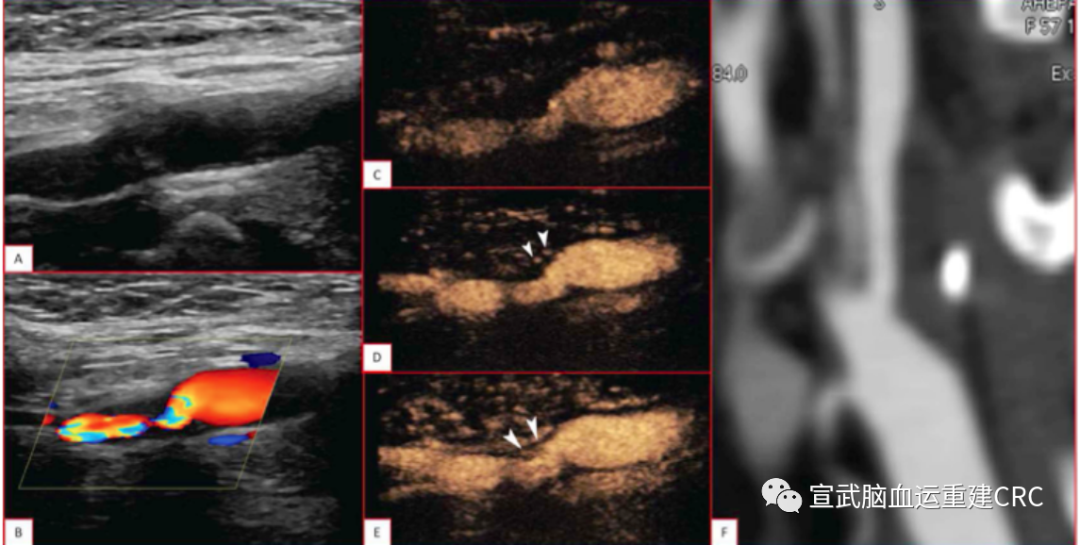

颈动脉的TOF-MRA成像中,斑块内高信号与支架术后新发梗死有很明显的相关性。即TOF出现斑块内高信号的病人在支架植入后,围手术期可能更容易出现新发的梗死。

TOF-MRA高信号→易损斑块(IPH)→NILs↑

Composite outcome of any stroke, death, or MI within 30 days was 8.1% (13/160) in the IPH group and 2.1% (5/239) in the non-IPH group (p<0.01)

The rate of postoperative infarct on DWI was 49.7% (75/161) for the IPH group and 33.6% (81/ 241) for the non-IPH group (OR=2.01, 95% CI 1.31 to 3.09, p<0.01).